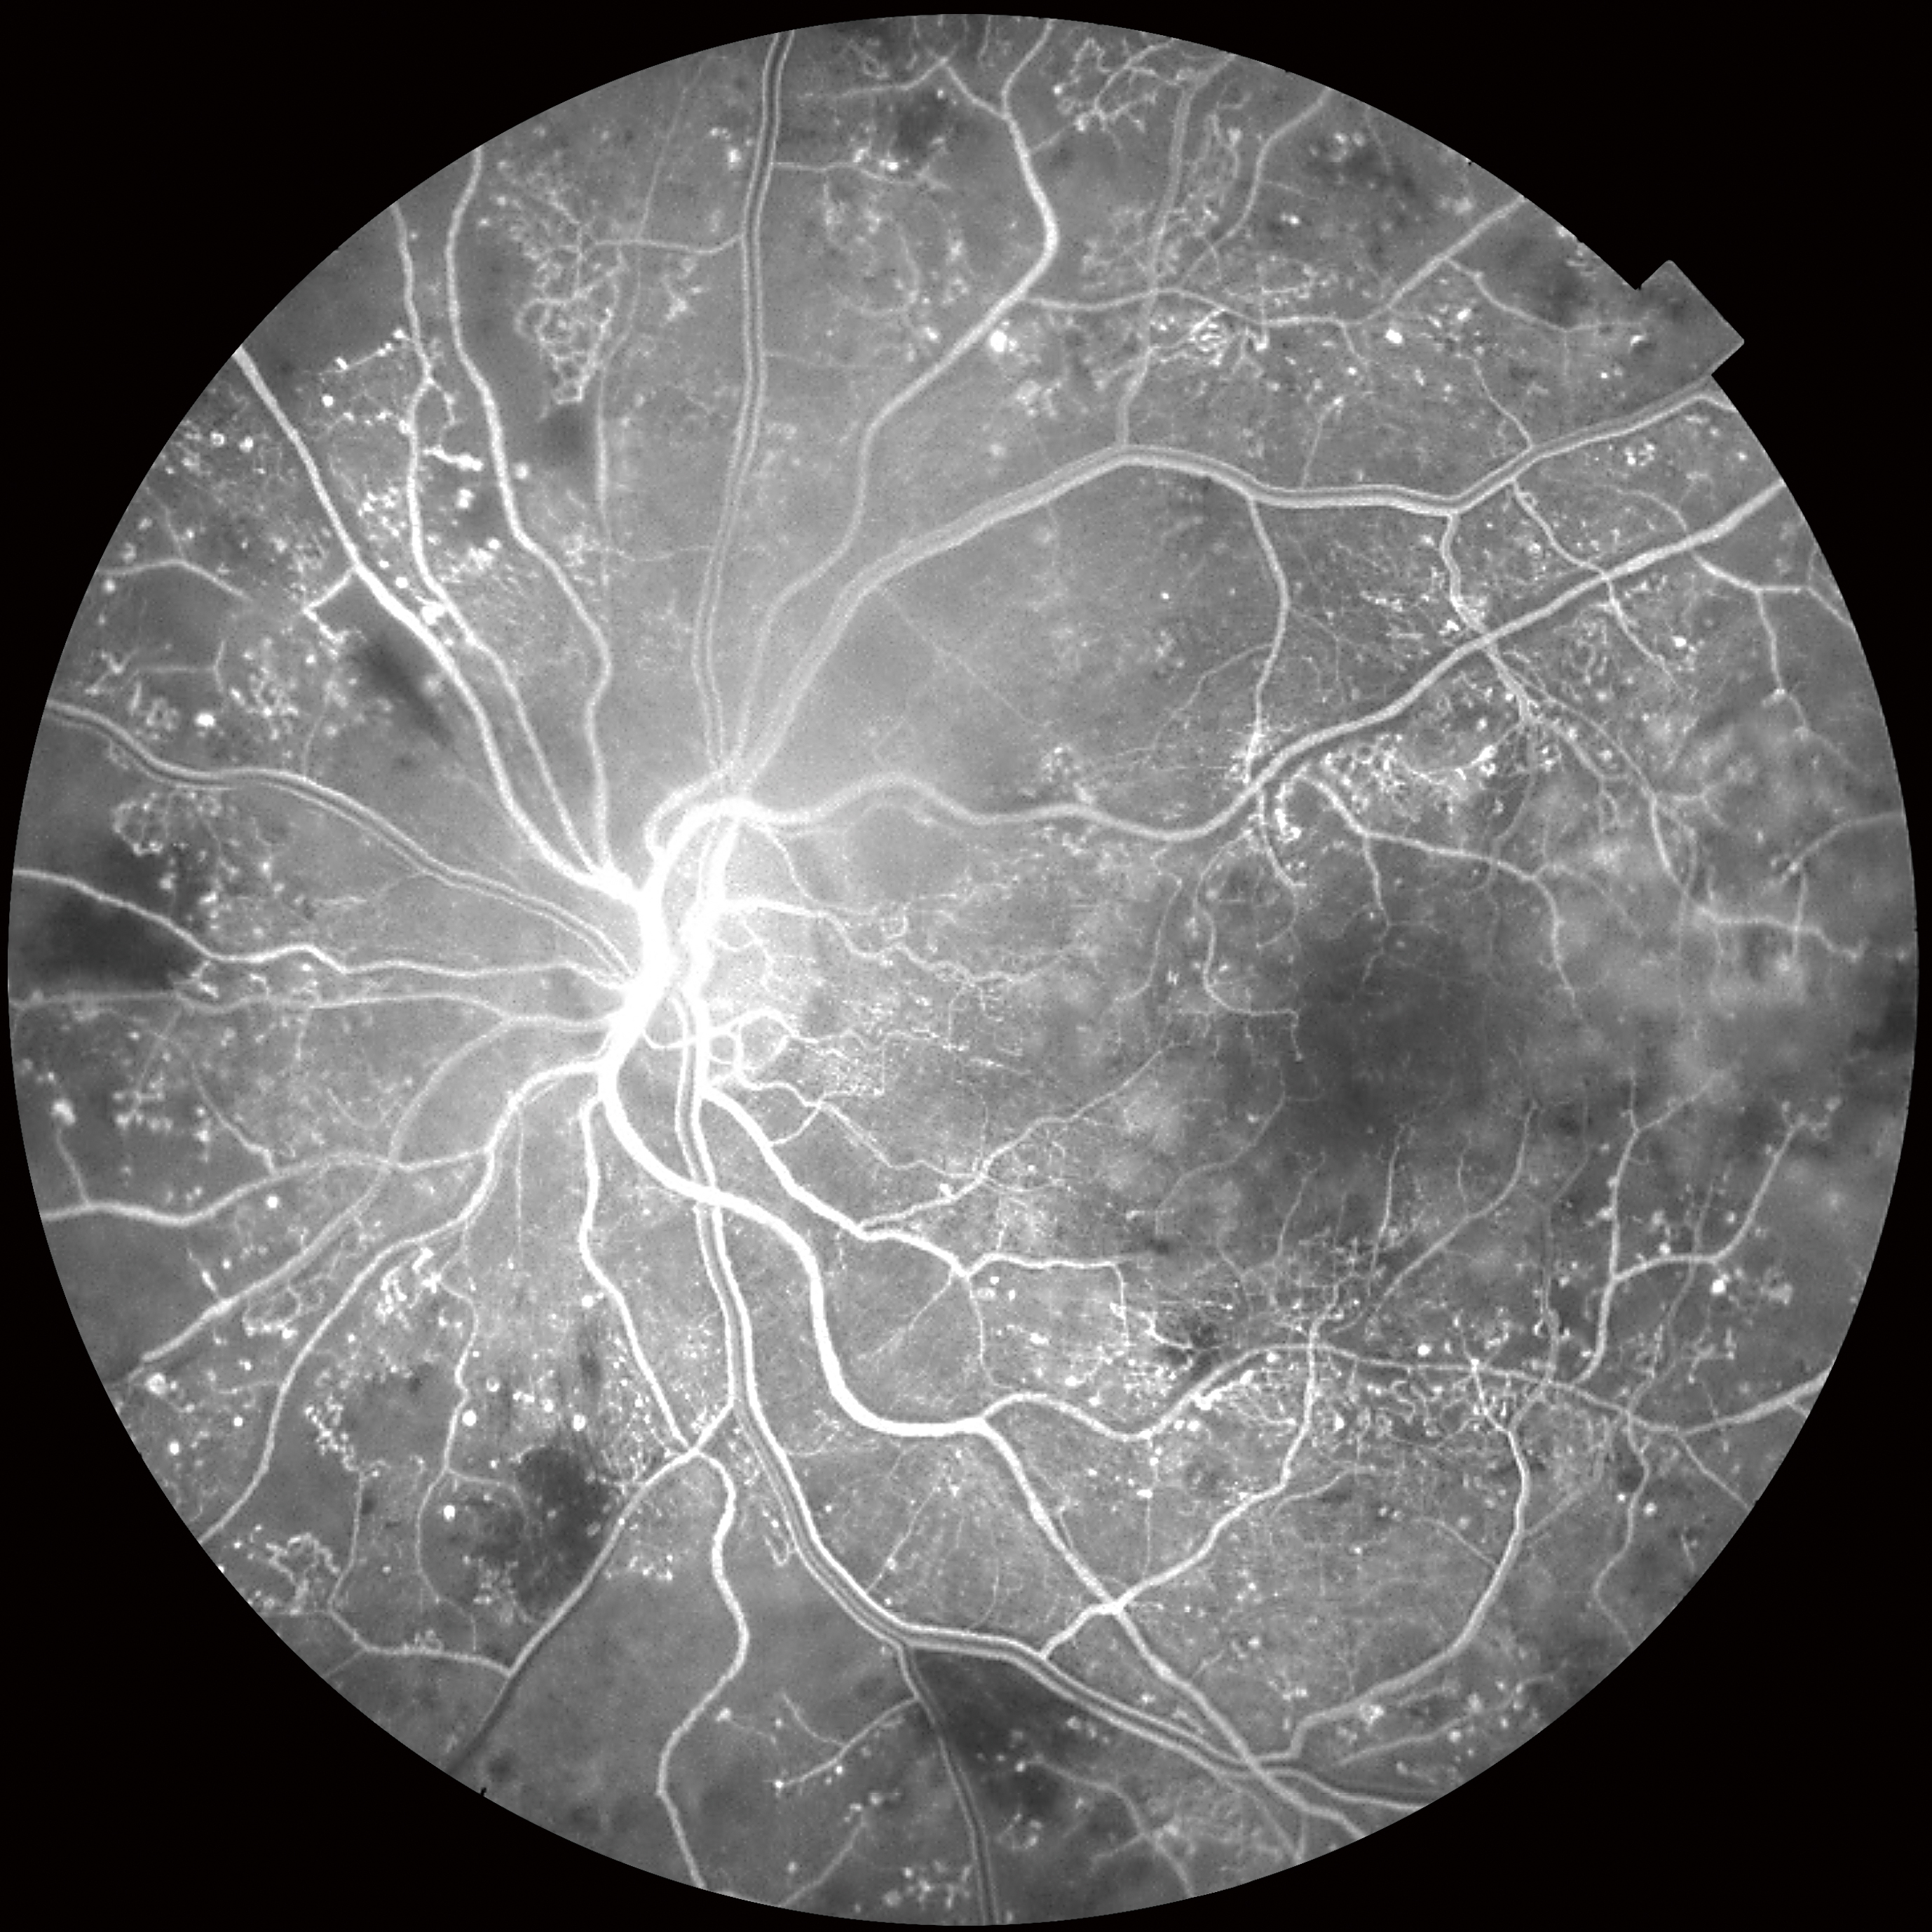

Triton с технологией Swept Source благодаря скорости сканирования 100 000 Асканов/сек и длине волны 1,050нм обеспечивает чёткую и детальную визуализацию глубоко лежащих слоёв сетчатки, в том числе хориоидеи и склеры1.

- Улучшенная визуализация глубоких слоев заднего отрезка, включающих хороидею и склеру за счет инфракрасного источника света 1050 нм, в том числе в случае помутнений в оптических средах

- Скорость сканирования 100 000 А-сканов/сек. обеспечивает сокращение процедуры сканирования, в том числе ОКТ- ангиографии

SWEPT source и длина волны сканирования 1050 нм

Уникальное сочетание нового механизма получения ОКТ-снимков SWEPT Source и сканирующего луча в инфракрасном диапазоне (1050 нм) позволяет получить качественный ОКТ снимок структур заднего отрезка глаза: стекловидного тела, сетчатки, хороидеи и склеры – на одном скане. Эта особенность сокращает время исследования за счет отказа от получения дополнительных снимков для получения снимков высокой четкости.

Большая проникающая способность инфракрасного излучения позволяет получить снимки даже в случае наличия помутнений в прозрачных средах глаза (катаракта, кровоизлияния и т.д.).

Мультимодальная диагностика

Помимо ОКТ и ОКТ-ангиографии прибор позволяет получить снимки глазного дна с помощью встроенной немидриатической фундус-камеры. Модель DRI TRITON plus оснащена также модулями флуоресцентной ангиографии (AF) и автофлуоресценции (FAF).

Уникальная система навигации позволяет определять локализацию каждого В-скана ОКТ на фундус-изображении и наоборот.